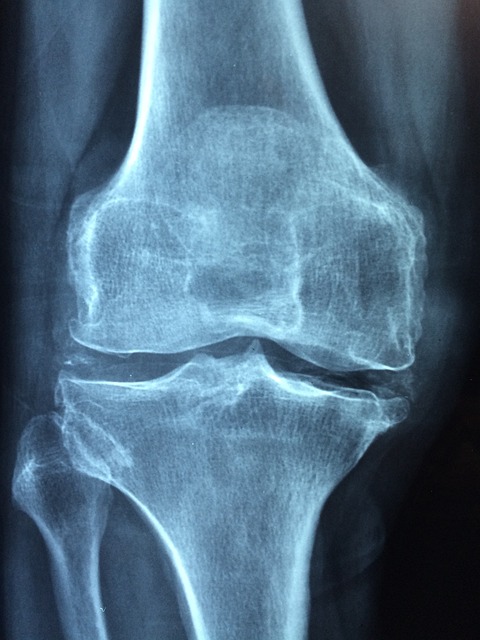

관절염은 관절의 염증으로 인해 통증과 부종을 유발하는 질환입니다. 이 질환은 여러 가지 형태가 있으며, 대표적으로 osteoarthritis(퇴행성 관절염)와 rheumatoid arthritis(류마티스 관절염)이 있습니다. 두 종류 모두 관절에 영향을 미치지만, 그 발생 원인과 증상은 다르게 나타납니다.

퇴행성 관절염은 일반적으로 나이가 들면서 발생합니다. 이 형태의 관절염은 관절의 연골이 마모되면서 점차 악화되는 현상인데요, 이는 오랜 시간 동안의 반복적인 스트레스나 과사용으로 인해 발생할 수 있습니다. 퇴행성 관절염은 무릎, 엉덩이, 손가락에 주로 발생하며, 증상으로는 통증, 뻣뻣함, 움직일 때 소리가 나는 등의 특징이 있습니다.

관절염 증상이 의심되면, 반드시 전문의와 상담하여 정확한 진단을 받아야 합니다. 조기 진단을 통해 필요한 경우 물리치료, 약물치료, 그리고 생활습관의 개선이 이루어질 수 있습니다. 전문가의 조언 아래에서 개인에 맞는 치료 계획을 세우는 것이 중요합니다.